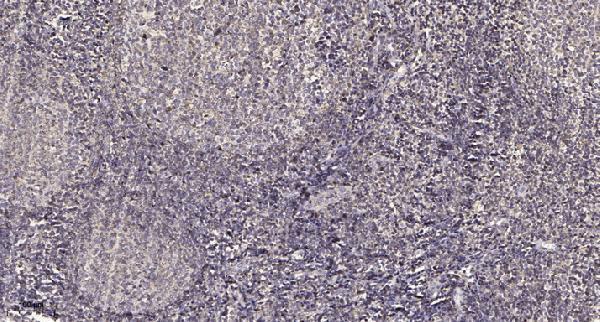

Immunohistochemical analysis of paraffin-embedded human tonsil. 1, Antibody was diluted at 1:200(4° overnight). 2, Tris-EDTA,pH9.0 was used for antigen retrieval. 3,Secondary antibody was diluted at 1:200(room temperature, 45min).